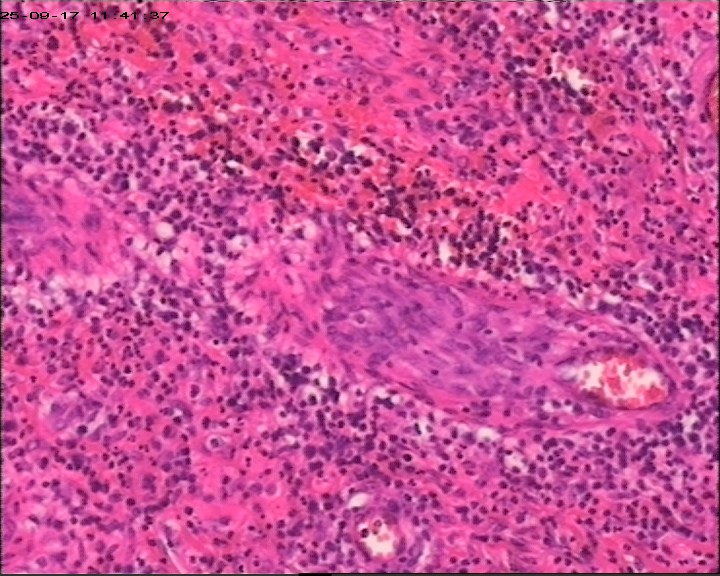

臀部组织,请帮忙看看,谢谢

性别

男

年龄

20岁

临床诊断

一般病史

藏毛窦或囊肿切开术

标本名称

臀部

灰白灰黄碎组织一堆,大小为6.5*4*1cm。

描述诊断炎性病变